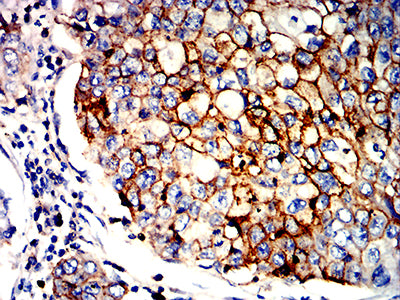

分类: 科研抗体货号: 32265别名:应用: IHC,IF,FCM反应种属: Human

分类: 科研抗体货号: 32287别名: FDH; FTHFD; 10-fTHF; 10-FTHFDH应用: WB,IHC,FCM反应种属: Human, Rat

分类: 科研抗体货号: 32291别名: hK2; hGK-1; KLK2A2应用: IHC,IF,FCM反应种属: Human